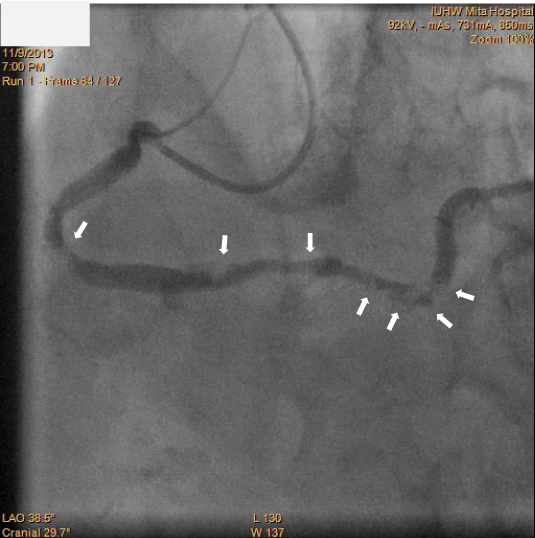

Figure2 Coronary angiography showing the right coronary artery before the percutaneous coronary intervention procedure.

Figure 4 Final images after the percutaneous coronary intervention procedure, with an abundance of fresh thrombus throughout the right coronary artery. White arrows indicate thrombus.